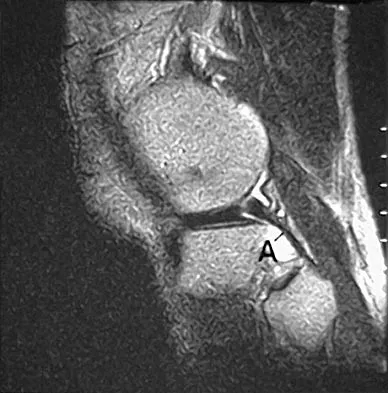

The primary function of structure "A" in Figure 29 is to limit

Explanation

The primary function of the popliteofibular ligament is to resist posterolateral rotation of the tibia on the femur, although it also secondarily resists varus angulation and posterior displacement of the tibia on the femur. The posterior cruciate ligament resists posterior tibial displacement, especially at 90 degrees of flexion. The lateral collateral ligament primarily resists varus displacement at 30 degrees of flexion but also resists posterolateral rotatory displacement with flexion that is less than approximately 50 degrees. The anterior and posterior cruciate ligaments resist varus displacement (along with the lateral collateral ligament) at 0 degrees of flexion. The anterior cruciate ligament primarily resists anterolateral displacement of the tibia on the femur. Sugita T, Amis AA: Anatomic and biomechanical study of the lateral collateral and popliteofibular ligaments. Am J Sports Med 2001;29:466-472.

References:

- Veltri DM, Deng XH, Torzilla PA, et al: The role of the cruciate and posterolateral ligaments in stability of the knee: A biomechanical study. Am J Sports Med 1995;23:436-443.